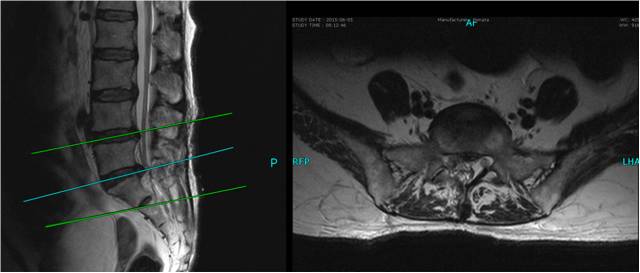

在完善了各项检查后,奚健副教授和丁锡平副教授为彭女士成功实施了右侧腰5到骶1神经粘连松解术。术中,专家们通过手术清除病灶和松解纤维神经血管束及其粘连,解除了对神经根的压迫,恢复了受损部位的微循环,促使神经功能最大程度地得到恢复。

图中箭头显示手术后复查MRI显示责任点神经恢复原形